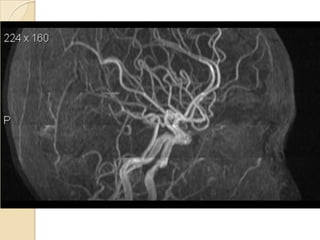

Arteries of the brain (lateral view) - MRA

1. Anterior cerebral artery

2. Anterior communicating artery

3. Basilar artery

4. branches (in insula) of middle cerebral artery

5. Cavernous portion of internal carotid artery

6. Cervical portion of internal carotid artery

7. Genu of middle cerebral artery

8. Intracranial (supraclinoid) internal carotid artery

9. Middle cerebral artery

10. Ophthalmic artery

11. Petrous portion of internal carotid artery

12. Posterior cerebral artery

13. Posterior cerebral artery in ambient cistern

14. posterior cerebral artery in interpeduncular

cistern

15. Posterior communicating artery

16. Posterior inf cerebellar artery.

17. Quadrigeminal portion of posterior cerebral

artery

18. Superior cerebellar artery

19. Vertebral artery